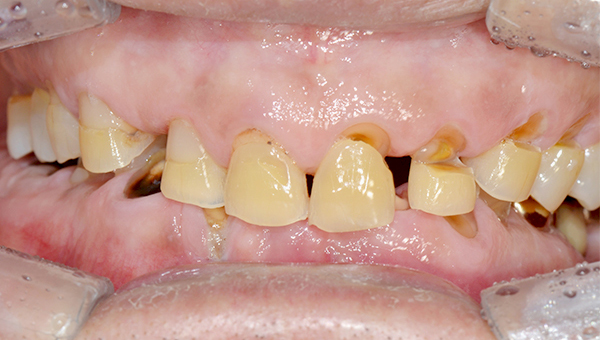

치료사례임플란트

박*수 임플란트 시술 사례

전체 임플란트

20**.**.**

치료 전

치료 후